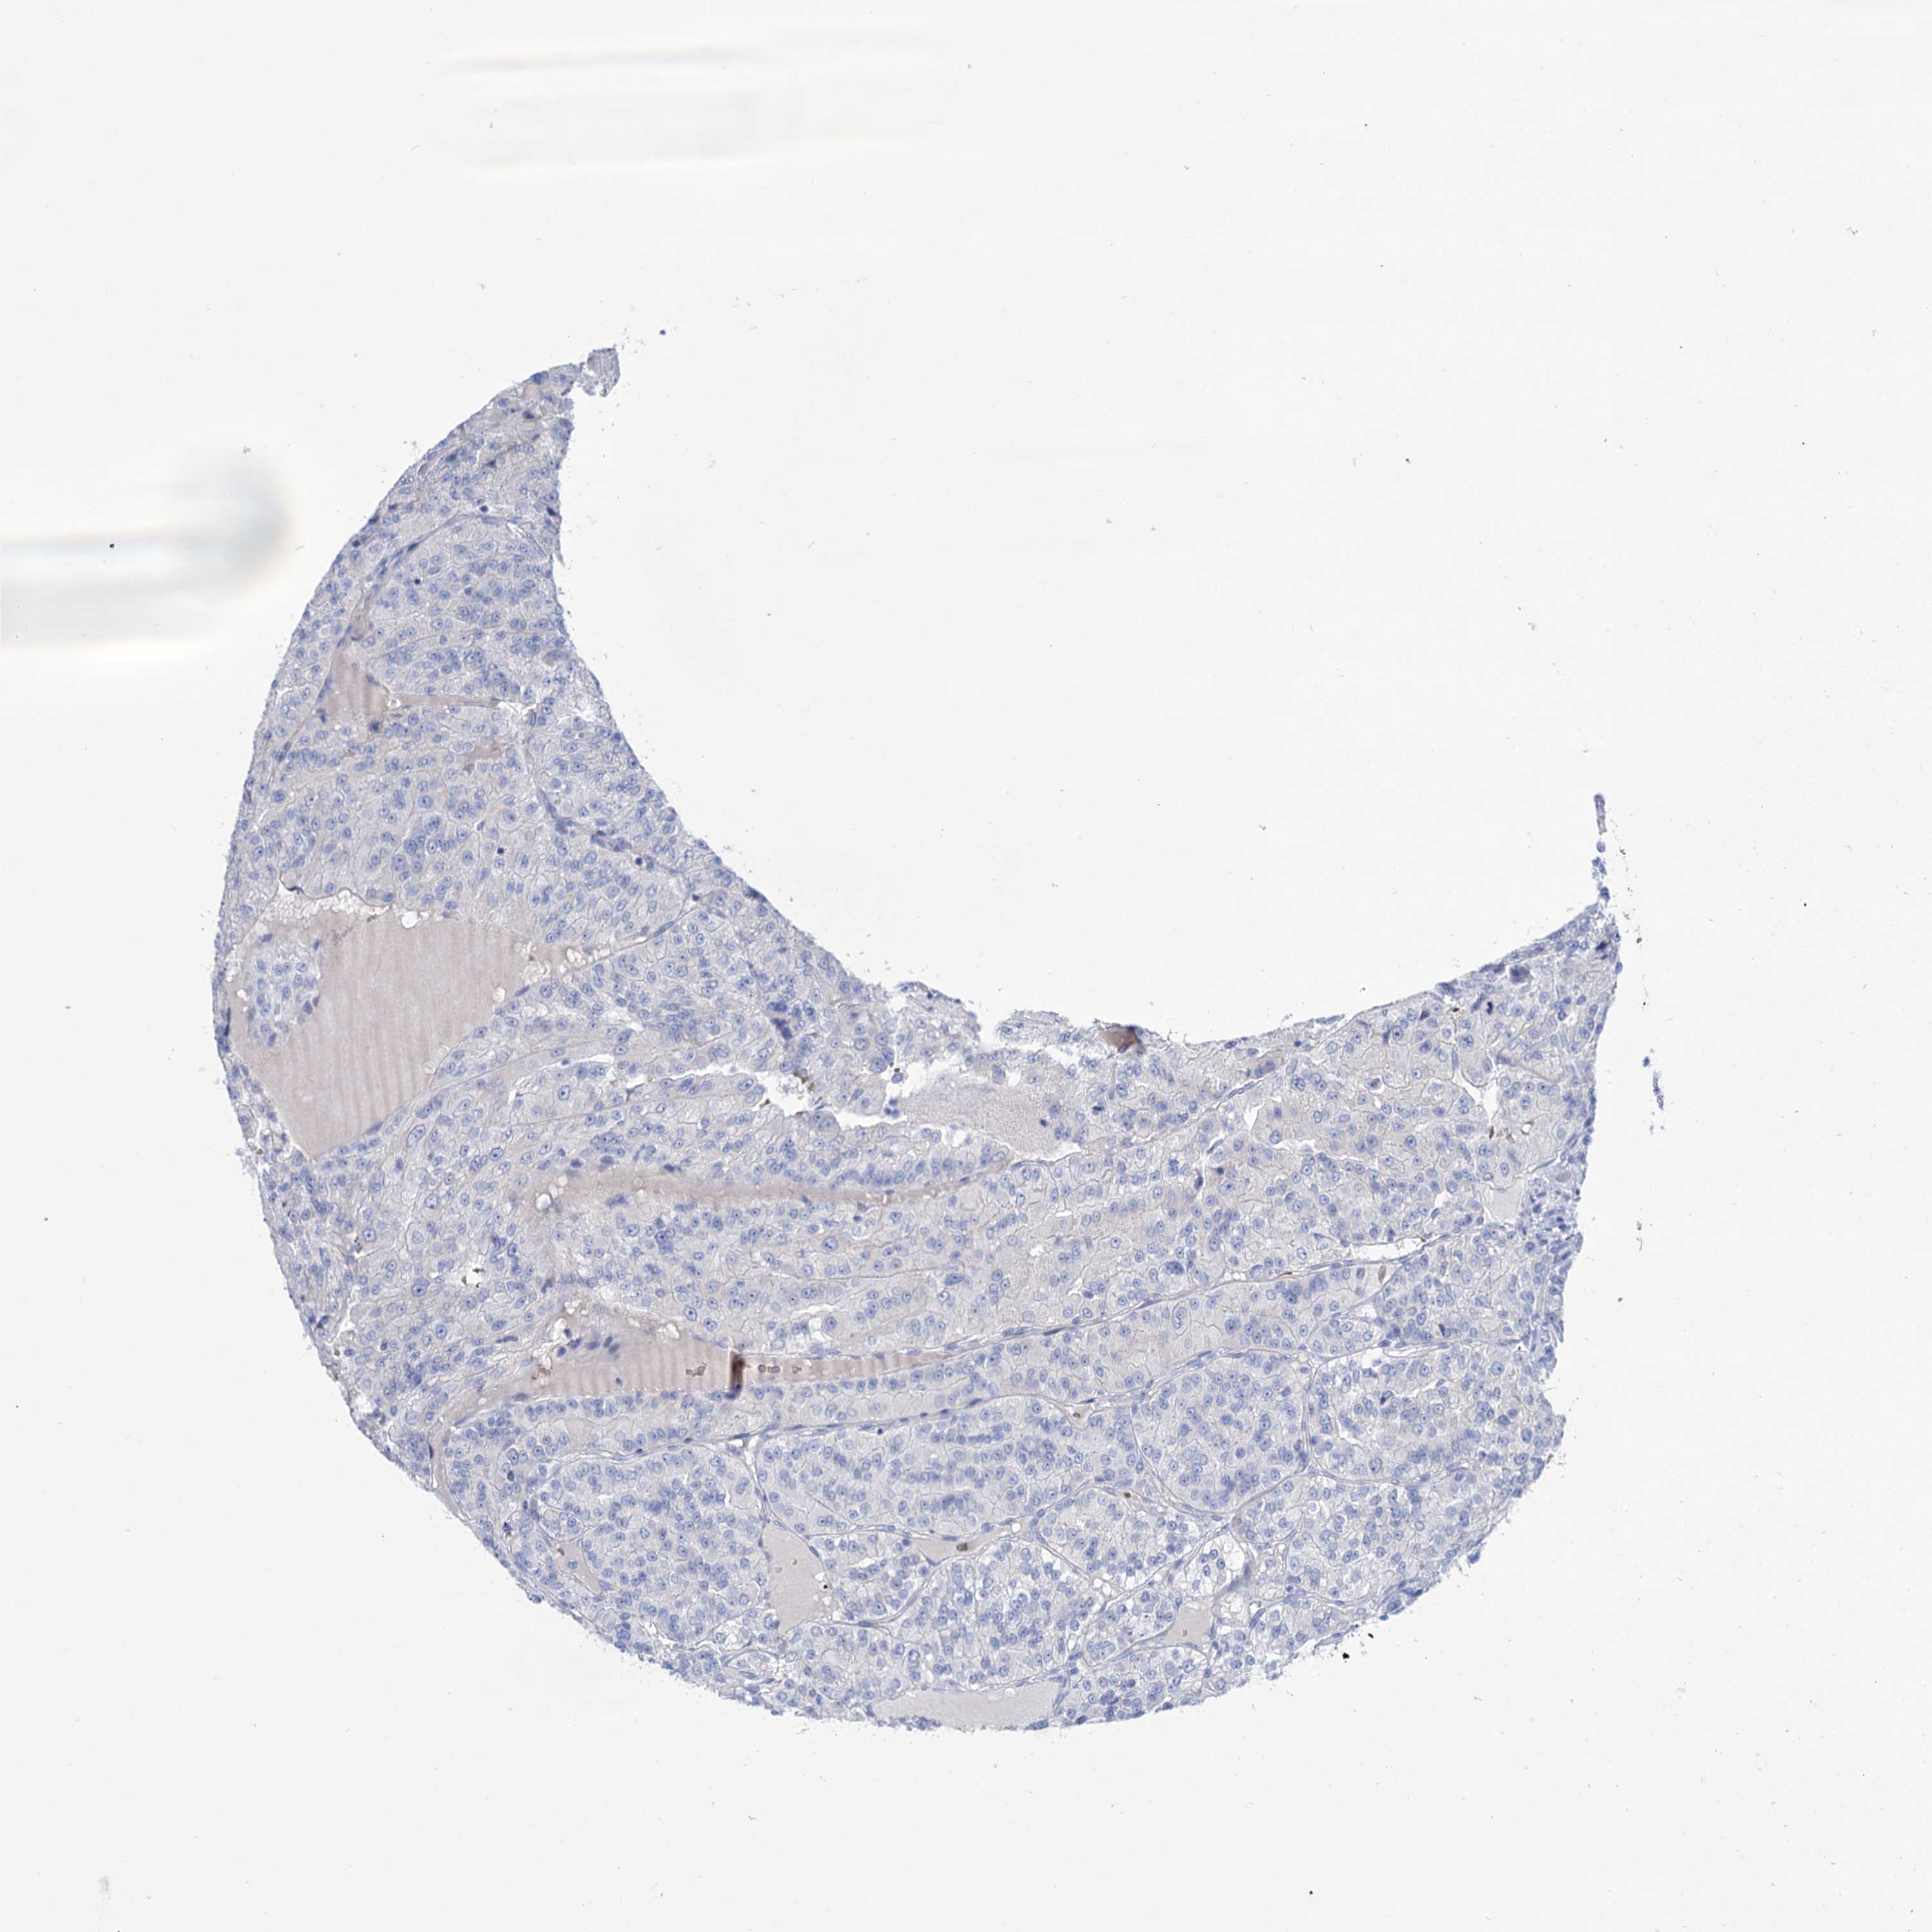

CANCER RENAL CANCER Show tissue menu

KICH TCGA KIRC TCGA KIRC VALIDATION KIRP TCGA PROTEIN RCC CPTAC PROTEIN EXPRESSION